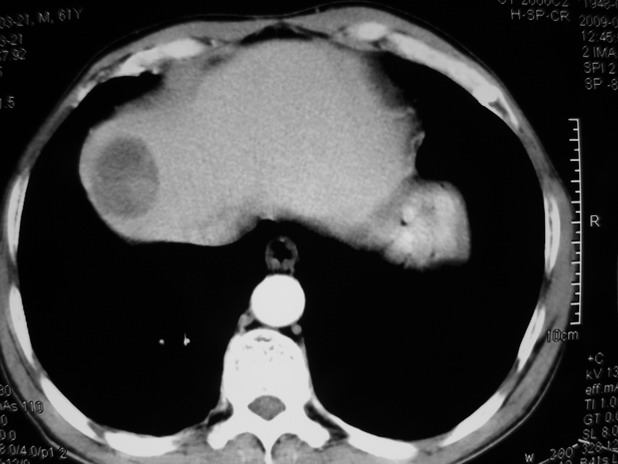

以下是引用余辉在2009-3-21 21:36:00的发言:[br]图像太乱了,建议楼主直接将强化数据按顺序列出来,病灶位置较表浅薄,有肝炎病史,灶内实性成分有显著强化,动脉期约60hu,考虑肝癌可能性大,进一步检查。